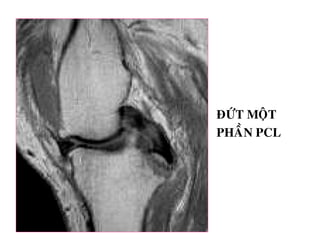

ÑÖÙT MOÄT

PHAÀN PCL